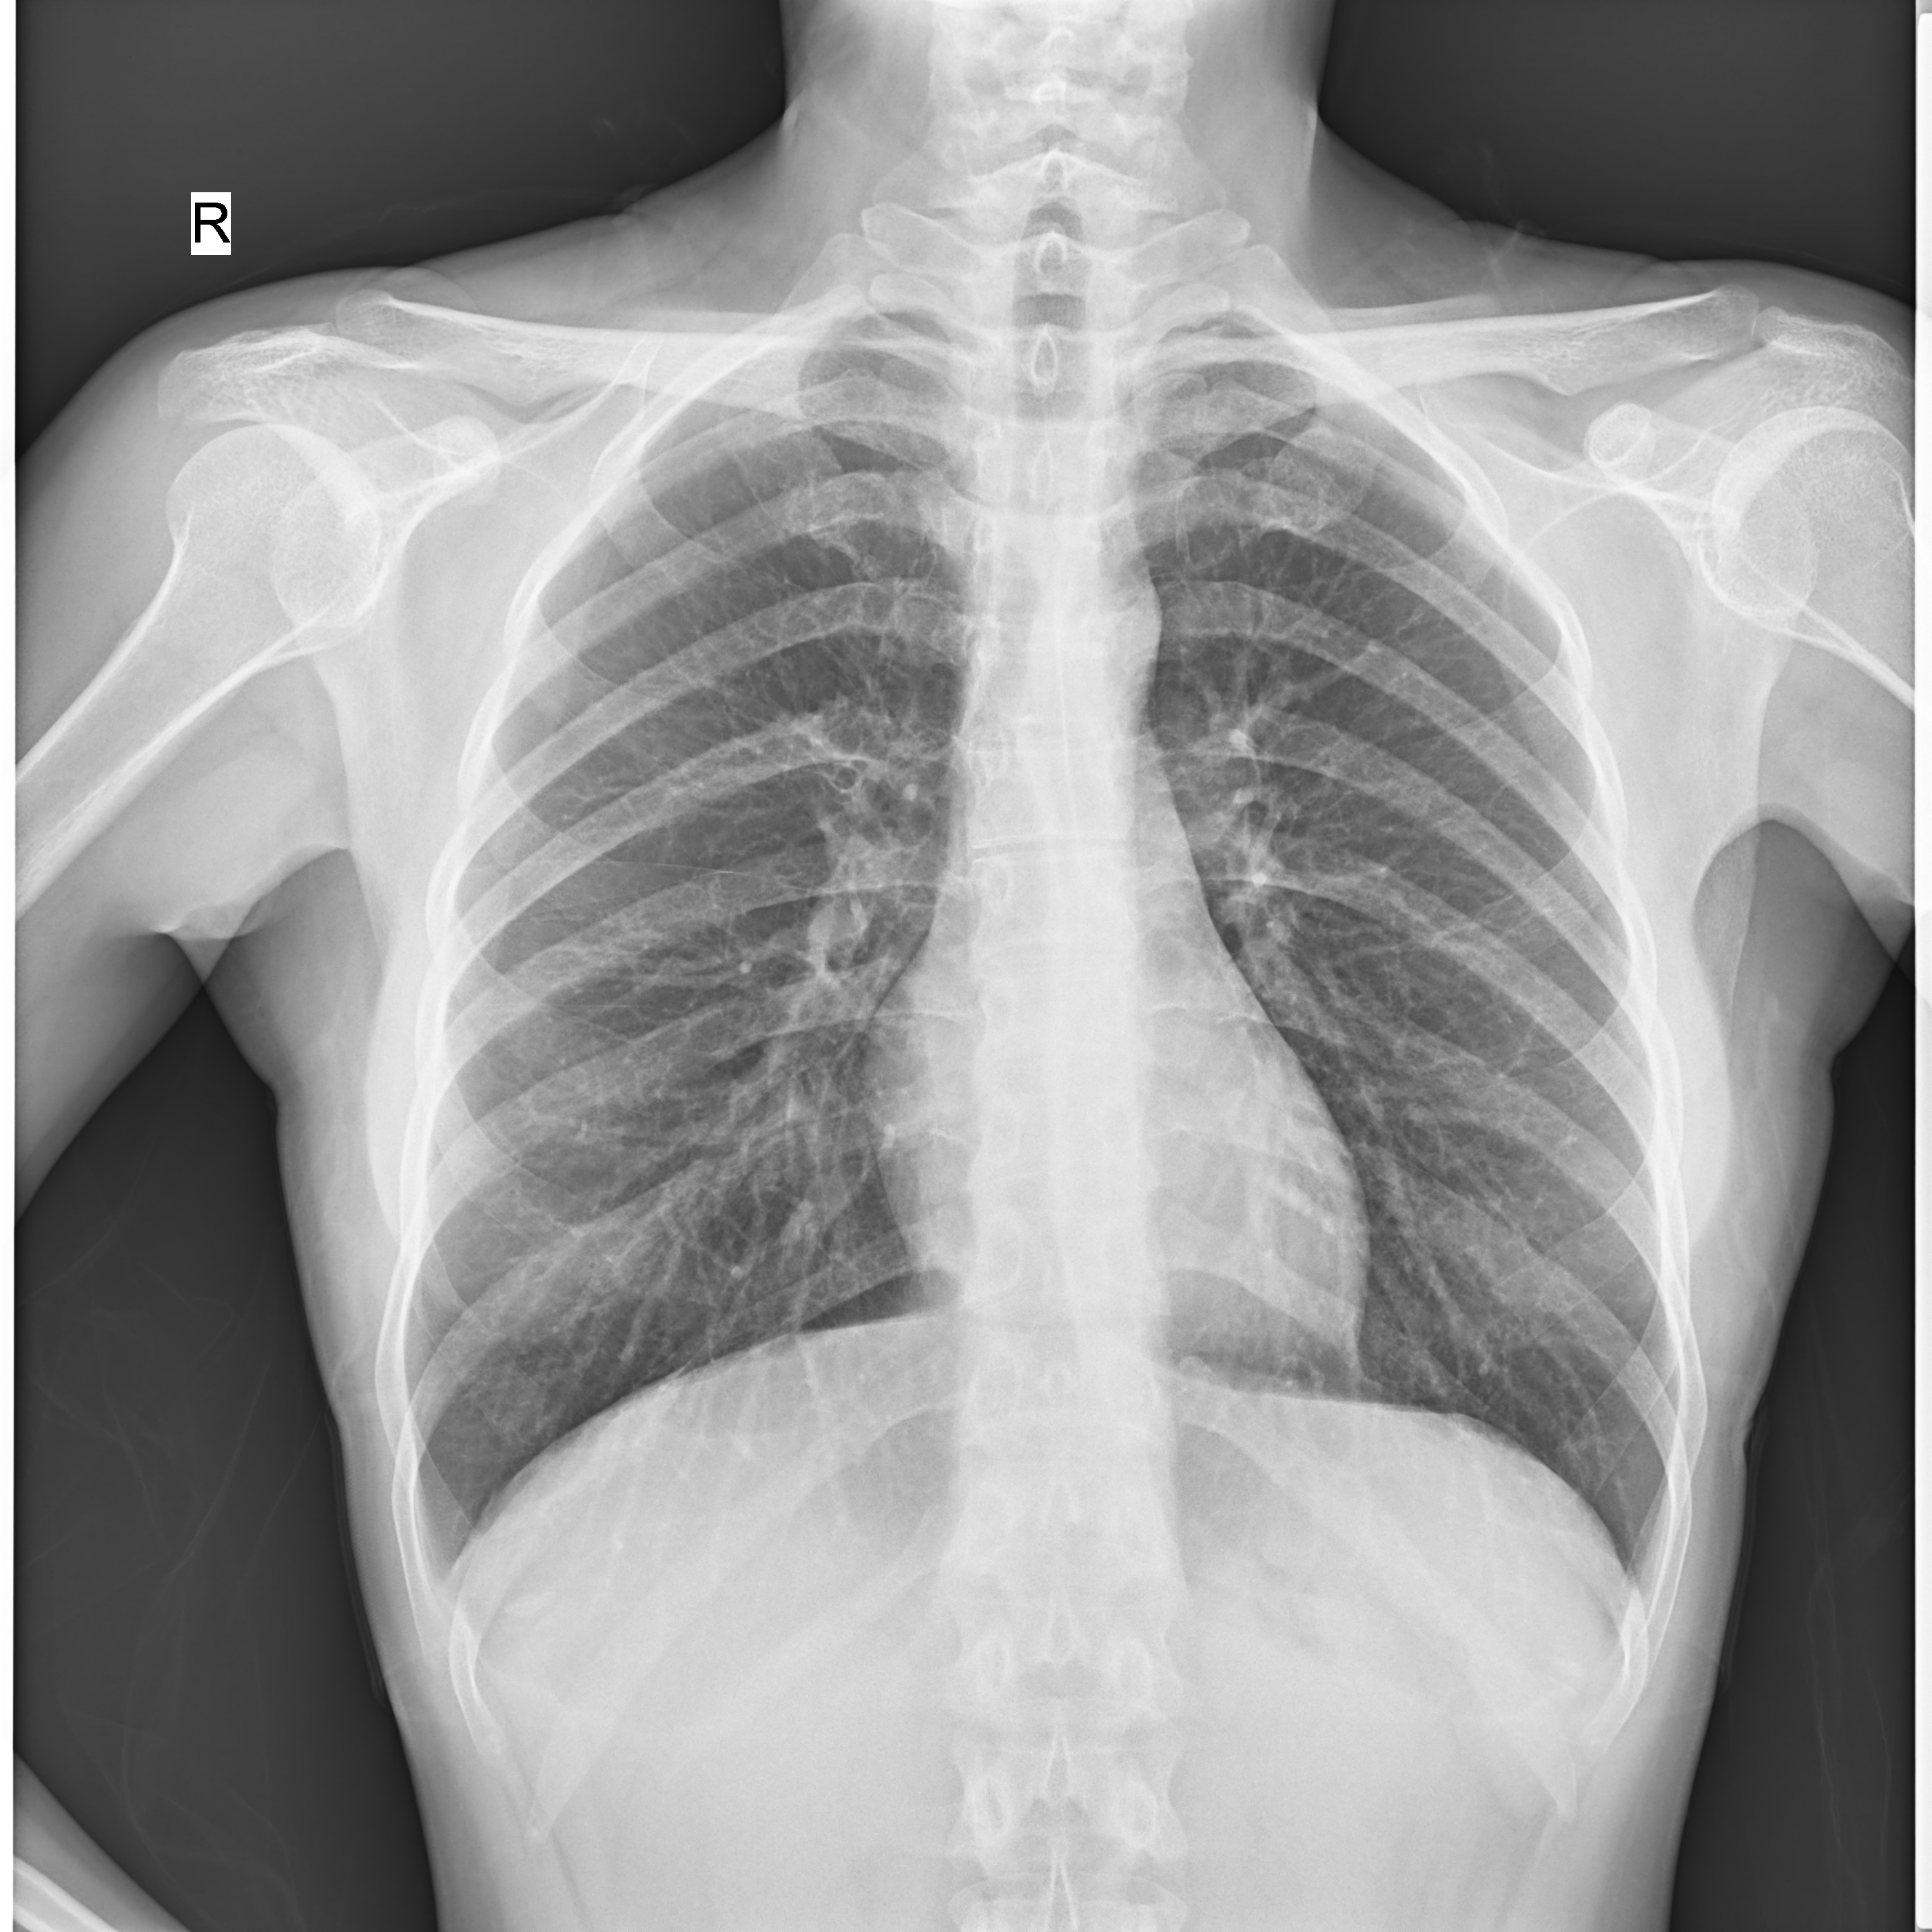

臨床圖片

高千伏攝影